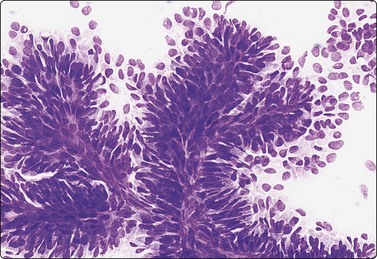

image image

Fig. 7.4 Non-neoplastic glandular breast tissue and low-grade duct carcinoma

High-power view, Pap-stained smears; (A) Bimodal population in smear from non-neoplastic breast; (B) Single and clustered cells in low-grade carcinoma; some single cells probably stromal (Pap, HP).